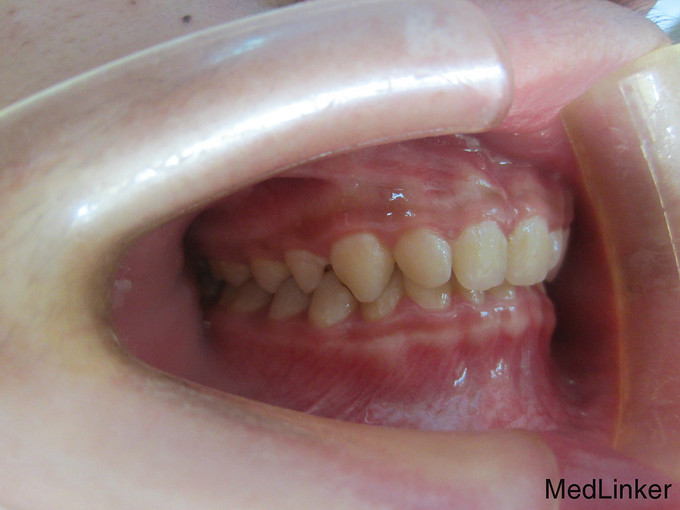

检 查:双侧颞下颌关节开口弹响,开口度一度; 模型测量分析:3度深覆合,上下颌轻度拥挤,spee曲线陡峭,上下颌尖牙尖锐、宽度较小,; 头 颅 侧位片:下颌平面角低角,下颌后缩,余正常; 辅 查:曲面断层片、头颅侧位片,双侧颞下颌关节片

诊断:深覆合、下颌后缩导致颞下颌关节负担加重,引起关节紊乱 治疗:一期:制作合平面导板,戴用一月后关节症状减轻,确定病因; 二期:带用固定矫治器,首先排齐上颌4个月,之后配合平面导板及摇椅弓排齐整平下颌5个月,调整上下颌咬合关系3个月,精细调整2个月,保 持1个月后拆除矫治器,患者自觉关节症状明显好转,制作保持器保持。